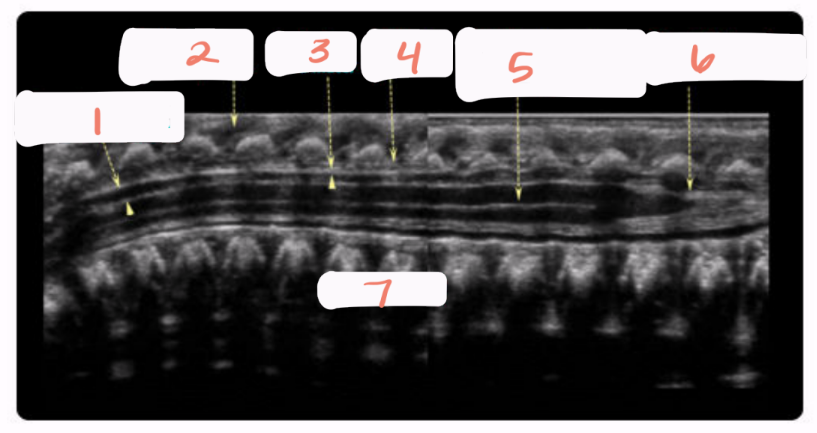

1

spinal cord

2

subarachnoid space

3

arachnoid and dura mater

4

cartilaginous spinous process

5

conus medullaris

6

central echo complex in hypoechoic spinal cord

7

vertebral bodies

8

nerve roots forming the cauda equina

solid white arrow

echogenic epidural fat